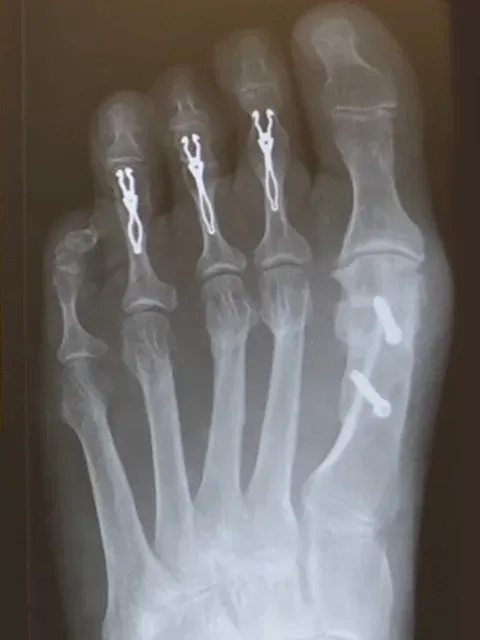

The bunion often affects the lesser toes too, causing problems with Claw toes, Hammer Toes and Metatarsalgia (pain under the ball of the foot). This will need addressing at the same time as the bunion surgery.

In more severe hallux valgus, there are often deformities in the lesser toes, with claw toes deformity or pain underneath the foot “metatarsalgia”. Both are due to the longstanding dysfunction of the big toe causing overload of the lesser toes. These deformities will need addressing at the same time and surgery can be complex, with multiple operations taking 1-2 hours.

Post op Left side & Pre Op Right side